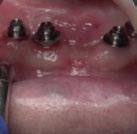

Figura 23. Férula quirúrgica inferior. Figura 24. Fresado guiado con férula y cucharilla. Figura 20. Extracciones dentales. 21. Conservación Figura 22. Férula quirúrgica superior. Figura 25. Inserción de implante RSX de Bego a través de férula quirúrgica. Figura 27. Conexión de pilar angulado multiplus sobre implante. Figura 26. Implante insertado en lecho a través de férula quirúrgica. Figura 28. Muestra del perfecto paralelismo tras la colocación de pilares angulados multiplus. Figura 29. ScanBody sobre pilares transepiteliales.

(Figuras 22 y 23). Se realiza fresado transgingival mínimamente invasivo y guiado hasta la inserción de los implantes, siguiendo el protocolo preestablecido e indicado (Figuras 24 a 26).

Dentro de la fase quirúrgica propiamente dicha, una vez terminada la inserción de los implantes y

comprobada su estabilidad primaria, colocamos pilares transepiteliales

Multiplus para registrar una impresión digital mediante escaneado sobre ellos (Figuras 27 a 29)